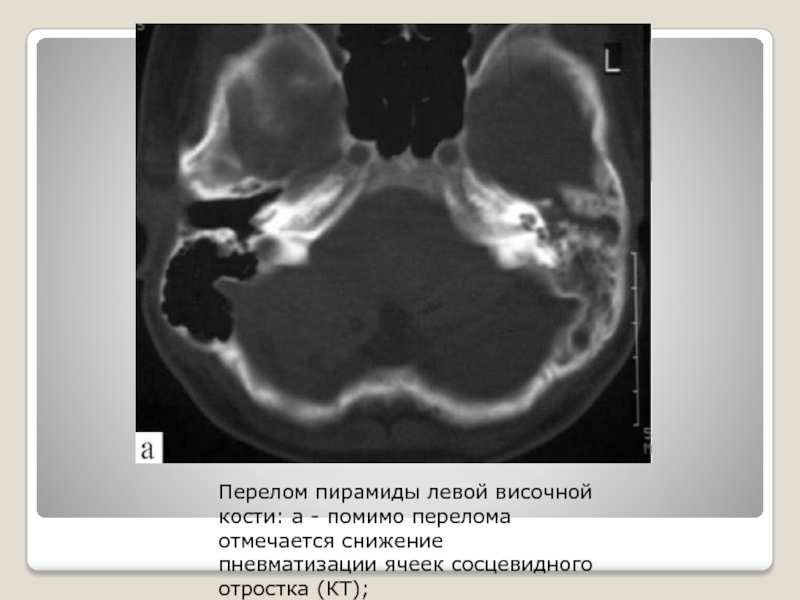

Слайд 19Перелом пирамиды левой височной кости: а - помимо перелома отмечается

снижение пневматизации ячеек сосцевидного отростка (КТ);

Перелом пирамиды левой височной кости: а - помимо перелома отмечается снижение пневматизации ячеек сосцевидного отростка (КТ);